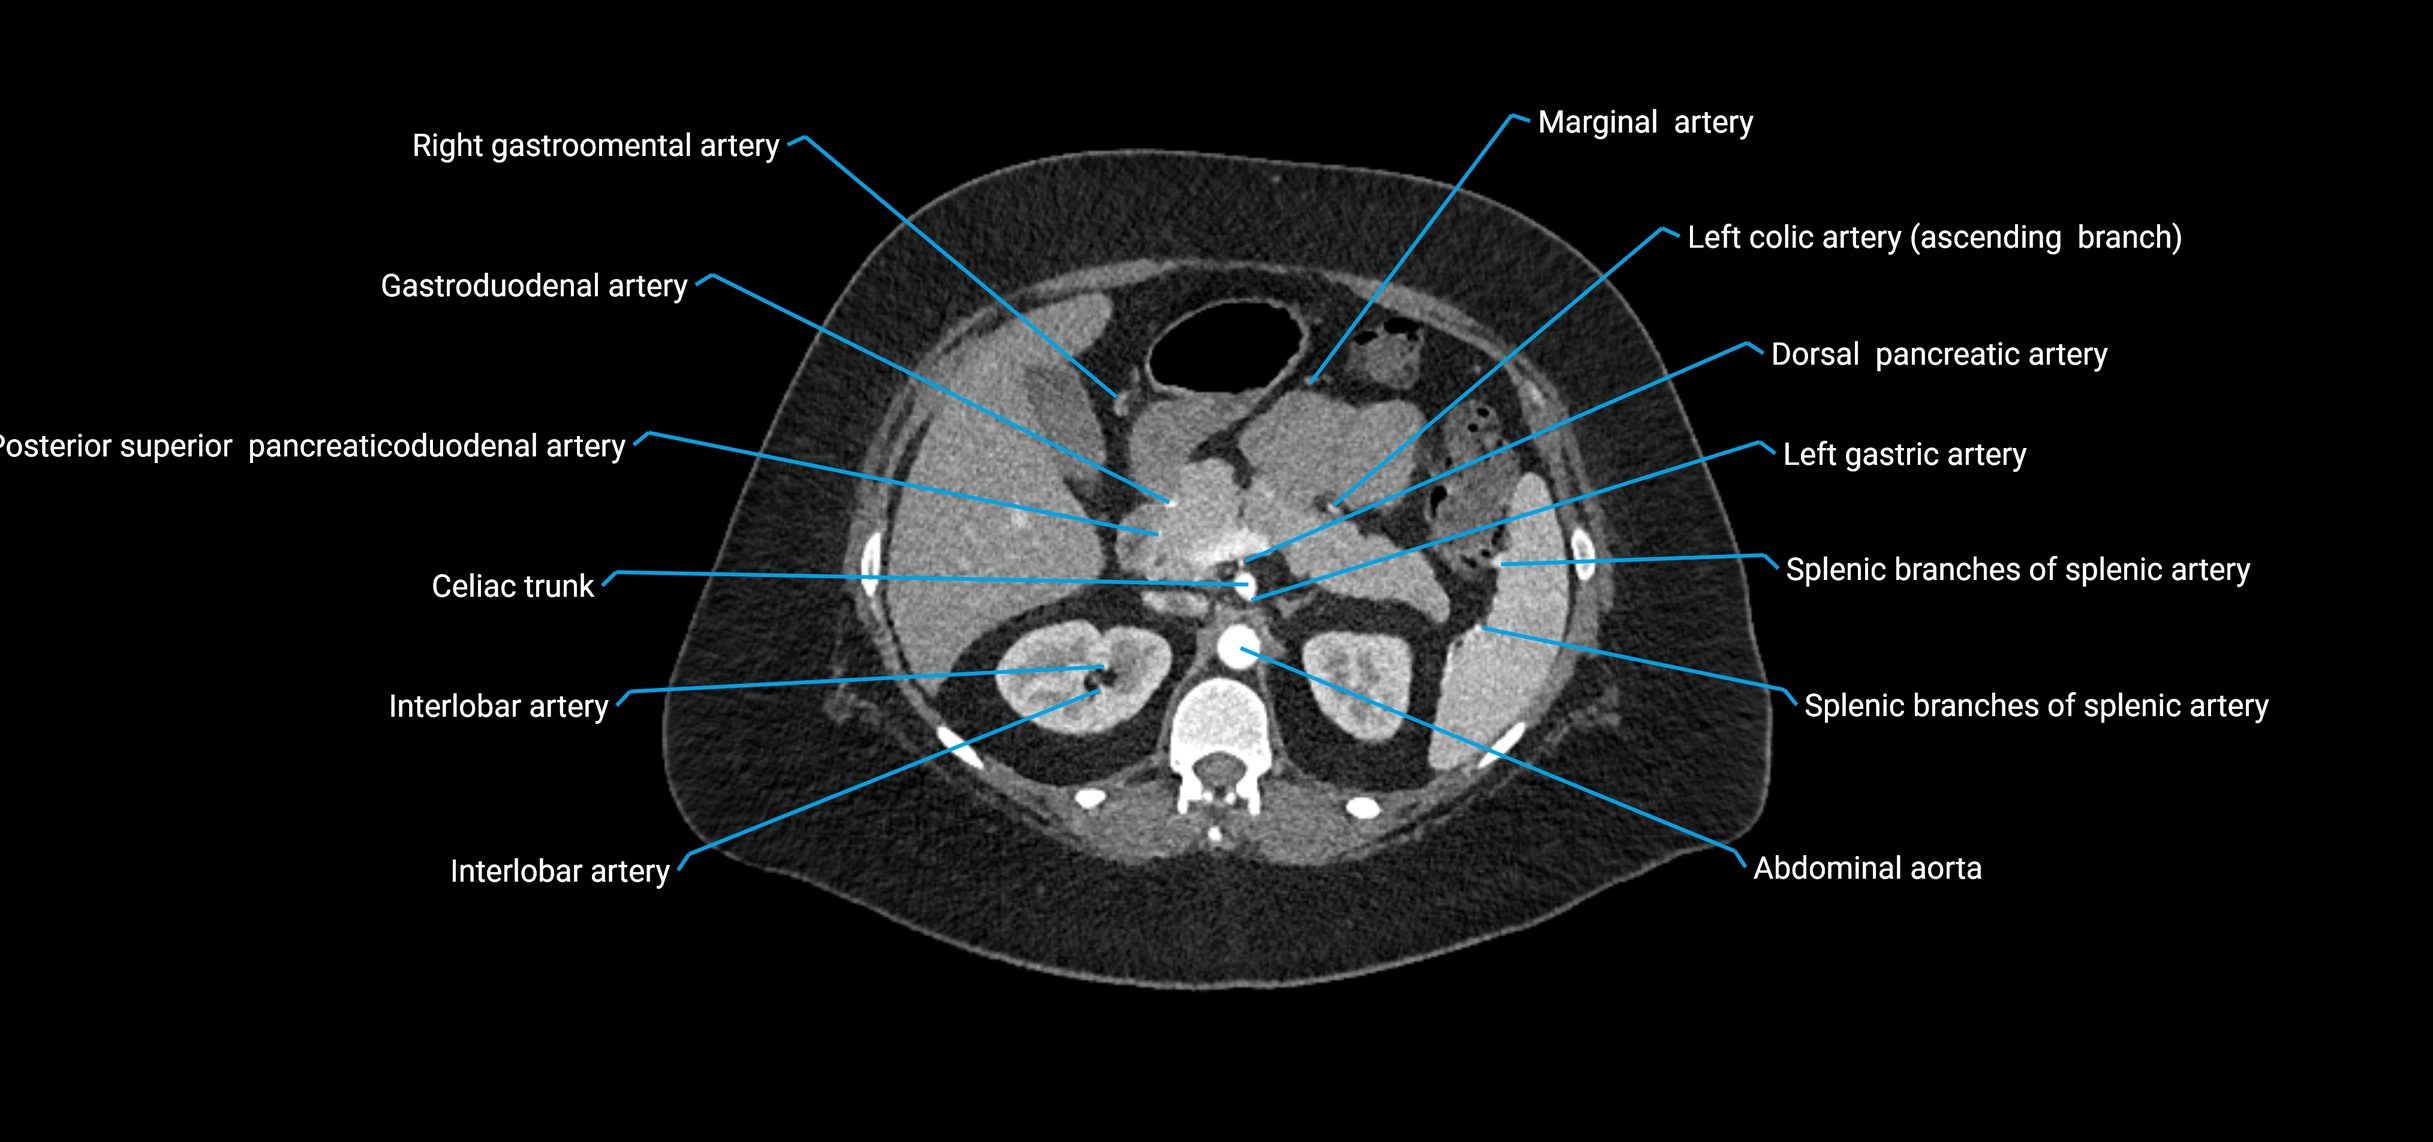

Contrast-enhanced CT (CTA):

• Gold standard for abdominal aortic imaging

• Provides excellent detail of lumen, wall, aneurysm, thrombus, and branch vessels

• Multiplanar and 3D reconstructions help in aneurysm measurement, stent graft planning, and dissection evaluation

• Detects acute rupture, traumatic injury, or occlusion with high sensitivity